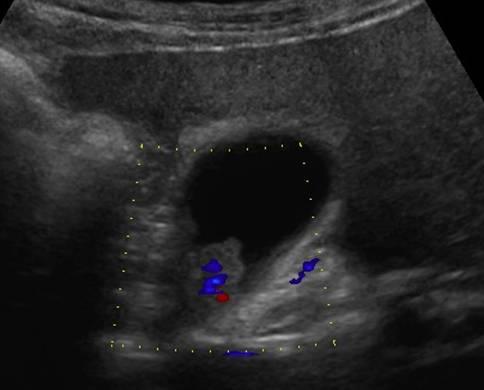

Ung thư túi mật

Ung thư túi mật - Ảnh 3

» Thông tin: Nam giới – 75 tuổi.

» Lâm sàng: Đau mạn sườn phải.